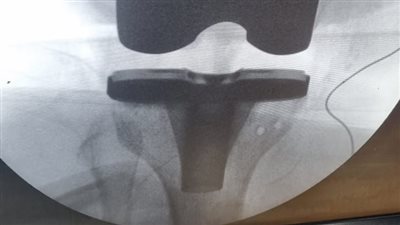

جراحة ناجحة لتغيير مفصل ركبة بمستشفى الزقازيق العام

الشرقية: إجراء جراحة متقدمة لتغيير مفصل ركبة كامل لمريضة بأبوحماد